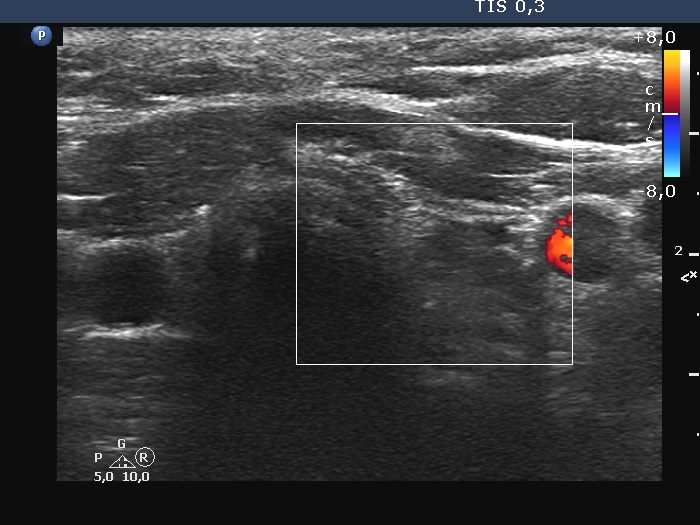

Follow-up investigation a year after the surgery (ultrasonographic picture 6)

Right lobe, longitudinal scan

Left lobe, transverse scan, color Doppler mode. The hypoechoic area is avascular.